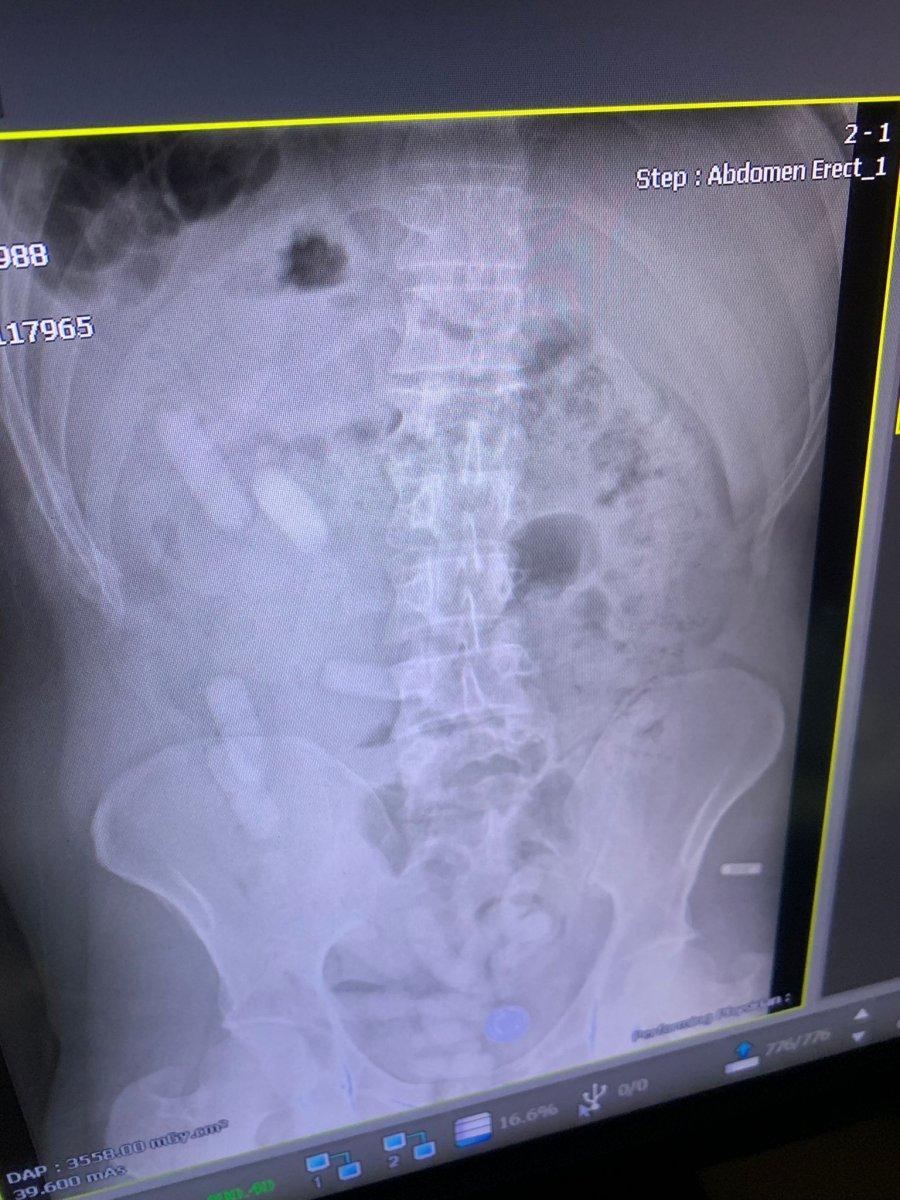

Şüphe ile A.E. isimli İranlı şahsa çekilen röntgen filminde, midesinde de 15 kapsül olduğu anlaşıldı.